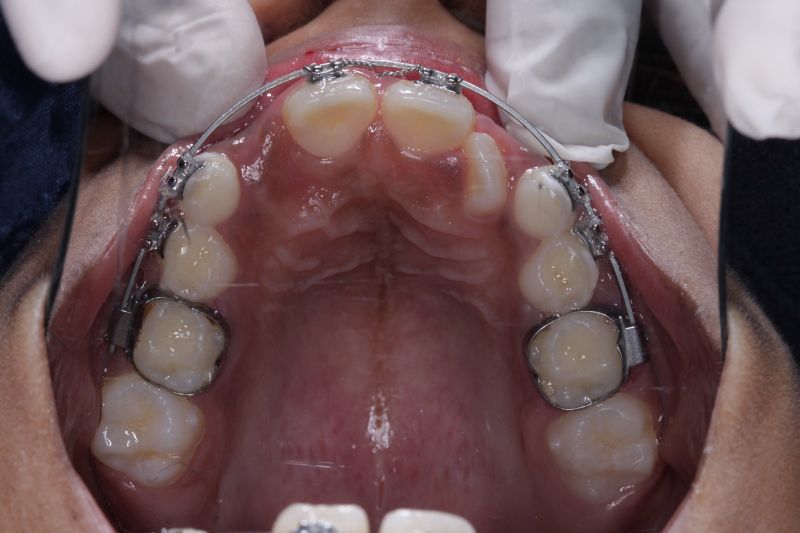

Early braces treatment correct the irregularly placed teeth and create room for erupting permanent teeth. correct bite problems such as open bite, cross bite and improves the appearance and self esteem of the child.